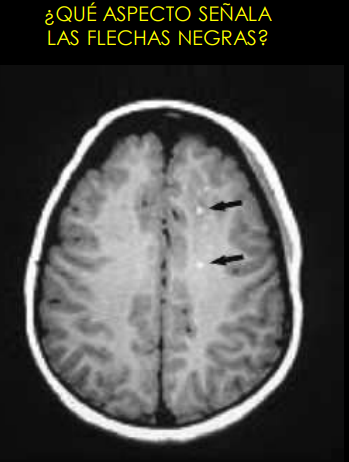

term image

Hiperintensos